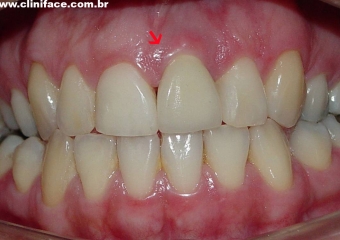

Sorriso inicial

Dente 21 com fratura